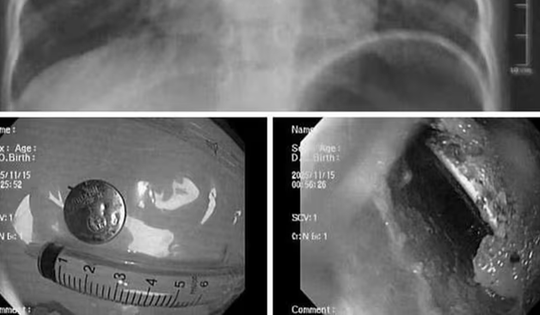

Bé trai bị loét sâu thực quản, bác sĩ gắp ra thứ "đáng sợ" bên trong

19/11/2025 19:00

Bé trai đang tuổi hiếu động vô tình nuốt phải vật dụng quen thuộc. Khi nội soi, bác sĩ ghi nhận vùng niêm mạc bị ăn mòn, gây loét thực quản.

Bé trai bị loét thực quản, bác sĩ gắp ra thứ "đáng sợ" bên trong